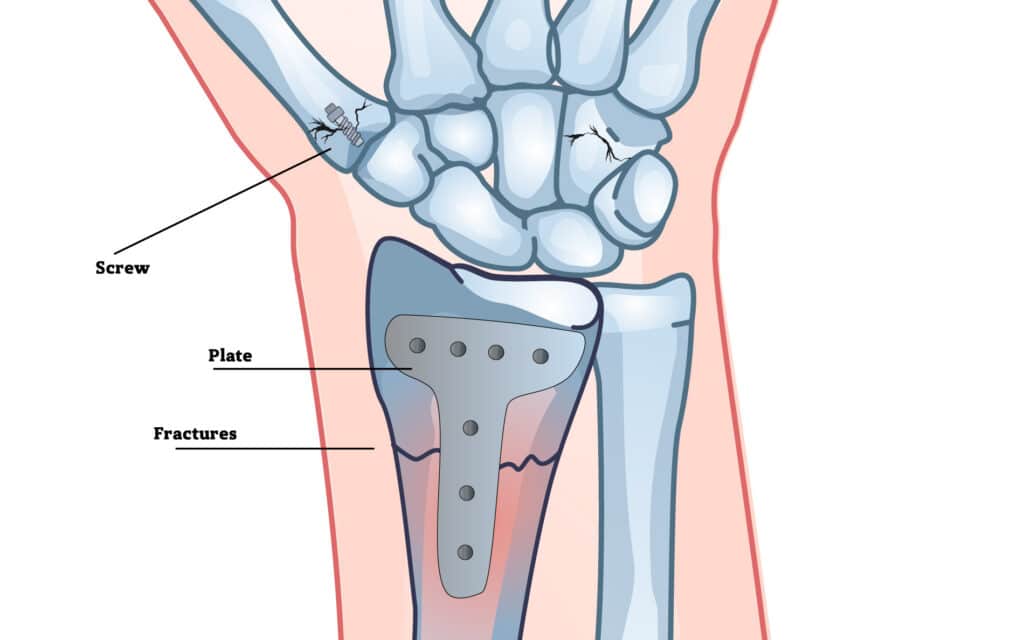

How Fractures are Treated

Reducing The Fracture